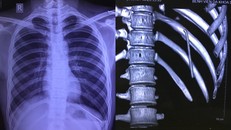

Hình ảnh chiếc đinh trong khoang phổi nam bệnh nhân. (Ảnh: BVCC)

(Ngày Nay) - Chiếc đinh tự di chuyển từ vai xuống khoang màng phổi khiến nam thanh niên đau nhiều vùng đáy phổi trái, khó thở, phải nhập viện.